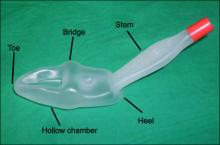

The second image shows the so called supraglottic airway device. The latest design is penis shaped:

But there are others: